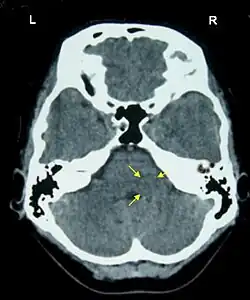

Хамер утверждал, что эмоциональные конфликты отражаются в тканях мозга возникновением «хамеровских очагов» — кольцеобразных структур, будто бы видимых на томографических снимках мозга; по расположению и выраженности «очагов» на снимках мозга Хамер якобы мог определять затронутые органы, первопричинный конфликт и его стадию. Разработанная Хамером теория чрезвычайно сложна и включает в себя взаимодействие разных конфликтов в «идентичных» и «неидентичных» стадиях; особое внимание уделяется преобладающей руке пациента. Хамер использовал при диагностике заболеваний собственную необычную номенклатуру наподобие «абсанс с вовлечением надкостницы» или «язвенная эпилепсия интимы коронарной вены». По утверждению Хамера, традиционная онкология убивает людей вместо того, чтобы лечить — причиной смерти якобы становятся эмоционально травмирующие «диагнозы и прогнозы», и новые эмоциональные конфликты приводят к развитию метастазов. Хамер высказывался против химиотерапии, лучевой терапии, хирургического удаления опухолей, даже использования обезболивающих при раке — лечение сводилось к поиску эмоционального конфликта, лежащего в основе заболевания; после его разрешения опухоль должна была пройти сама собой. Если рак у пациента продолжал прогрессировать, это объяснялось недостаточными усилиями больного по разрешению эмоционального конфликта[4].